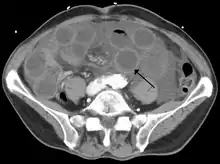

| Computed tomography (CT) showing dilated loops of small bowel with thickened walls (black arrow), findings characteristic of ischemic bowel due to thrombosis of the superior mesenteric vein. | |

Risk factors for acute intestinal ischemia include atrial fibrillation, heart failure, chronic kidney failure, being prone to forming blood clots, and previous myocardial infarction.[2] There are four mechanisms by which poor blood flow occurs: a blood clot from elsewhere getting lodged in an artery, a new blood clot forming in an artery, a blood clot forming in the superior mesenteric vein, and insufficient blood flow due to low blood pressure or spasms of arteries.[3][6] Chronic disease is a risk factor for acute disease.[7] The best method of diagnosis is angiography, with computed tomography (CT) used when that is not available.[1]